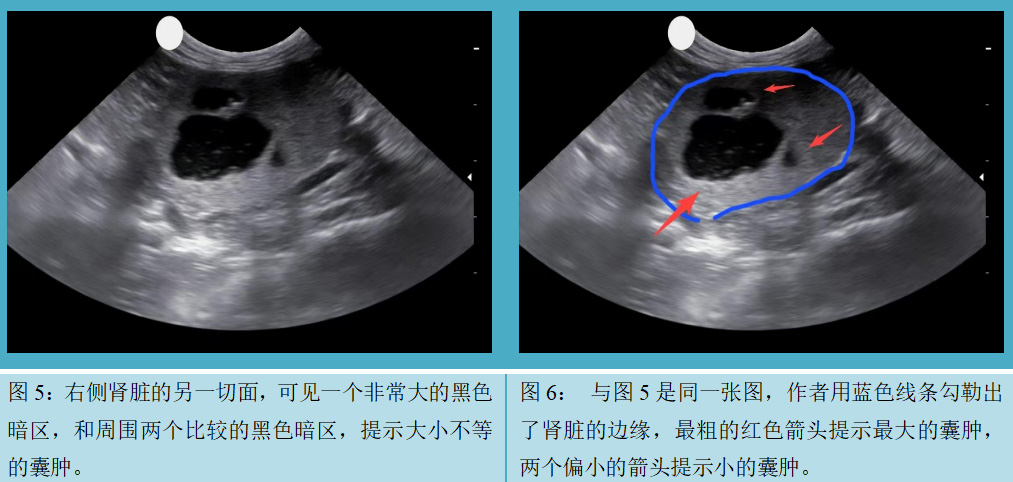

患者名叫TT,是一只去势的公加菲猫,7岁,体重1.9kg。TT在3月龄做腹部彩超体检时,发现肾上有多个很小的无回声暗区,提示多囊肾。当时猫的精神、食欲、大小便都没有异常,所以没有接受任何治疗,TT在5月龄的时候被现在的主人收养。大约3岁的时候,猫开始表现不太正常,每天喜欢睡觉,不爱玩耍。最近一年TT明显消瘦,体重从最重时候的4.5kg降到1.9kg. 同时食欲很差,被毛粗乱,经常腹泻。主人带TT到多个医院检查,进行腹部X片,血常规和生化检查等,但没有明显异常发现。经人推荐,TT转诊到作者的医院做腹部彩超检查,发现肾脏上多个囊肿(图1,图2,图3,图4,图5和图6),胃肠道未见明显异常,西医诊断为多囊肾。建议主人做其他相关检查,主人不想再给动物采血,也不想用其他西医方案,但是主人愿意尝试针灸。